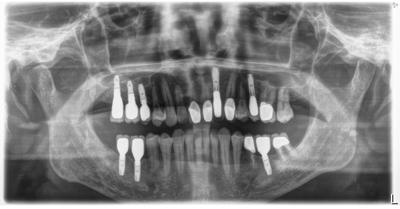

HOME > ブログ 一覧 > インプラント包括ケース 2021.01.26インプラント包括ケース 以前にご紹介したかも。 治療終了2年。 まだまだこれからのケース。 前医において対症療法的治療を繰り返し、状況がドンドン悪化して相談に来られ、当院で包括診療行ったケース。 上顎インプラントはサイナスリフト行っている。 補綴は全てセラミック。 よく分かっていない歯科医が安易に手を出すと悲惨な事にしかならない。 メインテナンスを責任持ってしっかり行って行きます。 Recent Entries アライナー矯正(インビザライン、シュアスマイル)費用を2023年 1月から改訂させていただきます(01/09) 本年もよろしくお願いいたします(01/02) 年始の診療について(01/01) 新しいWEBへ移行、年末年始の診療のお知らせ(12/29) ダラダラ根管治療行っても治らないという事(12/21) Category その他の治療(126) インビザライン・矯正(52) インプラント治療(216) ホワイトニング(47) メインテナンス(21) 包括診療(95) 医院からのお知らせ(249) 審美治療(128) 日々雑感(283) 根管治療(100) 歯周病治療(90) 矯正(73) 補綴治療(45) 補綴治療カテゴリを追加(1) 診療全般(44) Archive 2023年1月(3) 2022年12月(6) 2022年11月(14) 2022年10月(6) 2022年9月(8) 2022年8月(7) 2022年7月(13) 2022年6月(8) 2022年5月(7) 2022年4月(7) 2022年3月(6) 2022年2月(7)